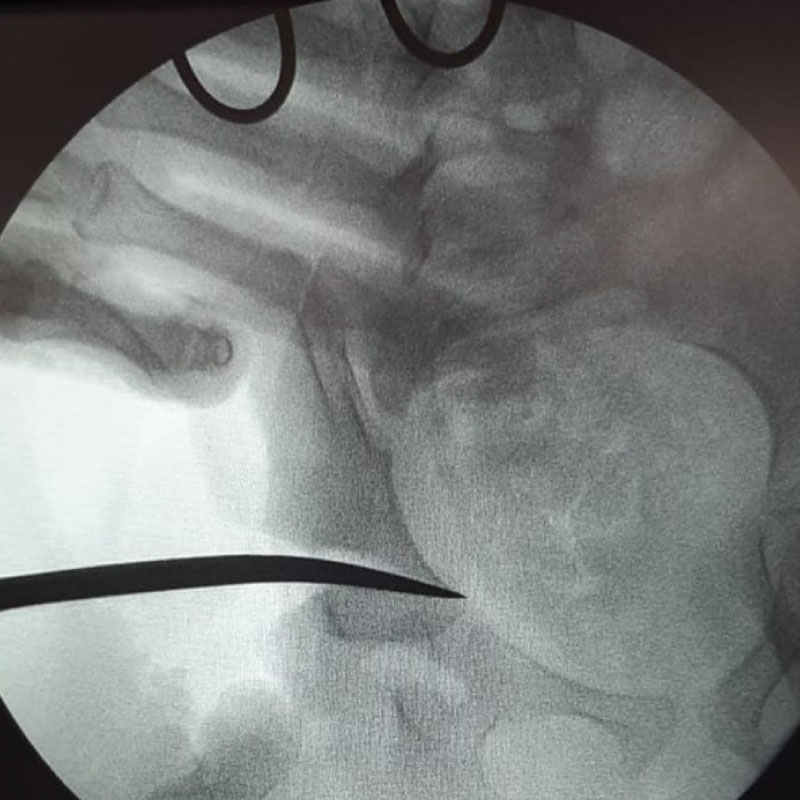

Caso No. 7 - Displasia de cadera derecha y síndrome down

Paciente femenino de 4 años de edad. Rx preoperatoria

Transoperatoria de Acetabuloplastia

Diagnóstico: Síndrome de Down con Displasia de cadera derecha con luxación.

Posoperación luego de la reducción abierta

Tratamiento quirúrgico realizado: Rx posoperatoria luego de la reducción abierta, acetabuloplastía y acortamiento femoral.